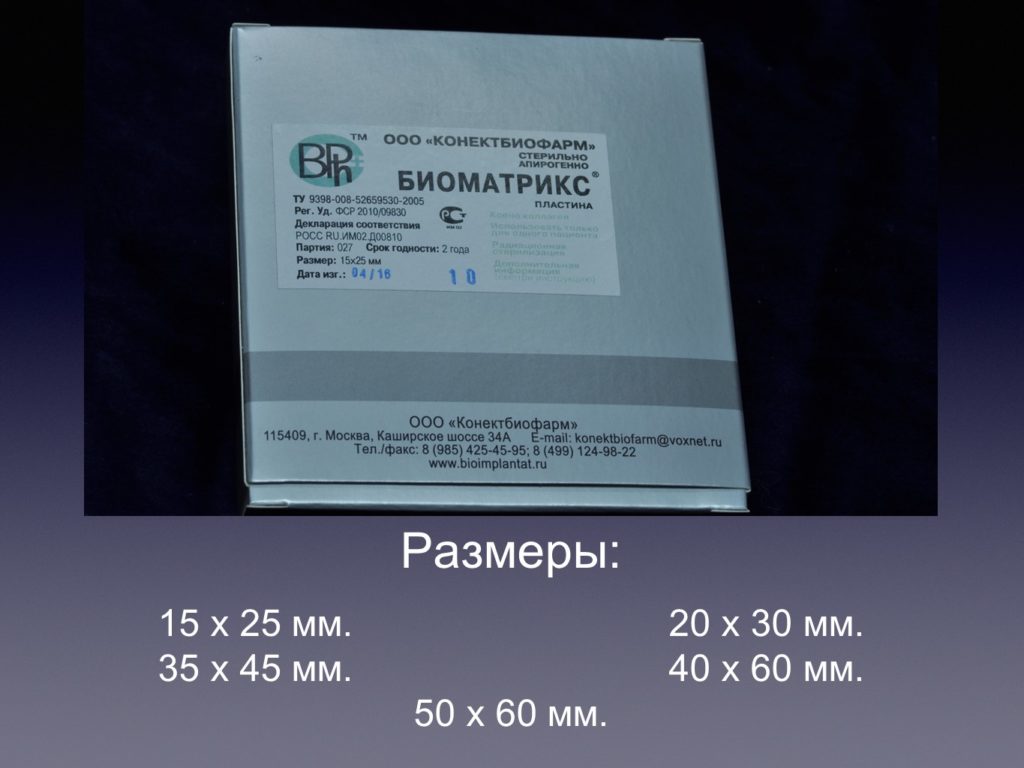

Принцип направленной костной регенерации. Костная регенерация под защитой мембраны Биоматрикс

Принцип направленной костной регенерации. Костная регенерация под защитой мембраны Биоматрикс

Принцип направленной костной регенерации. Костная регенерация под защитой мембраны Биоматрикс